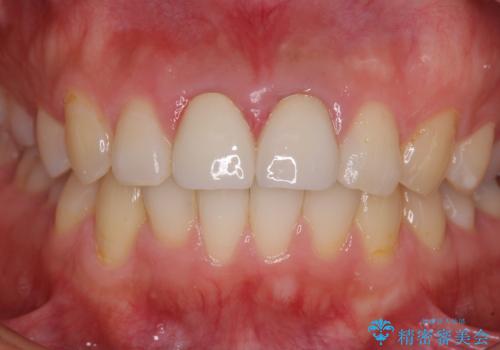

下顎前歯の部分矯正に半年ほどかかってしまい、少し期間は長いものとなりましたが、上下ともに前歯がきれいに整い、患者様には大変満足していただきました。